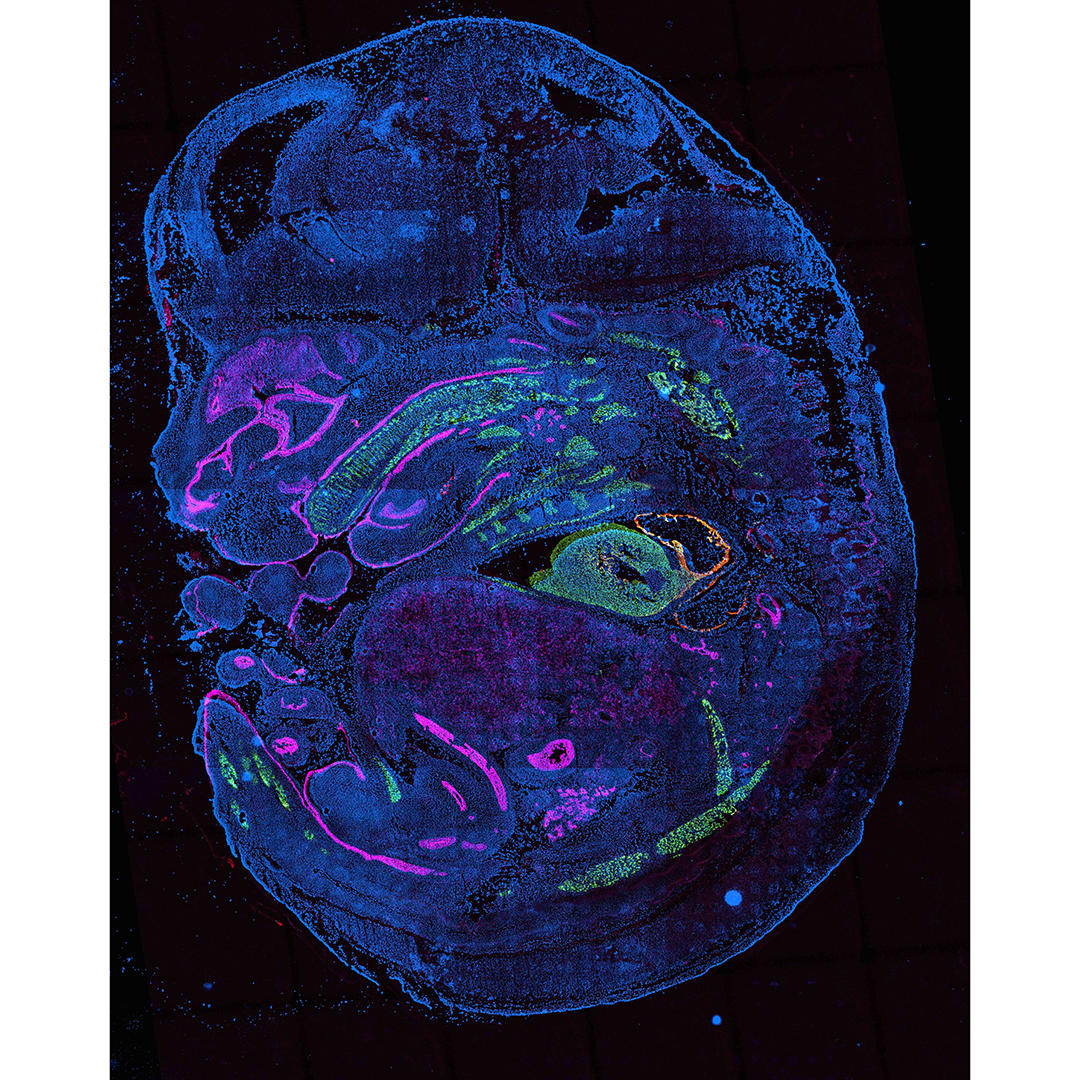

Sci-Space image of mouse embryo (stage E14), from Dr. Cole Trapnell at UW